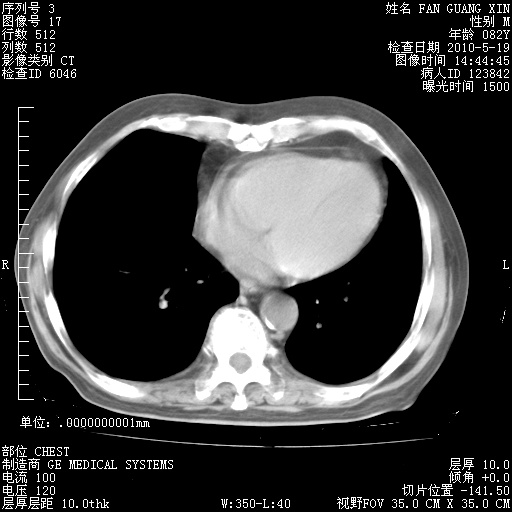

可改为口服强的松40-50mg/d治疗,若病情仍稳定,胸部阴影不再吸收可逐渐减量